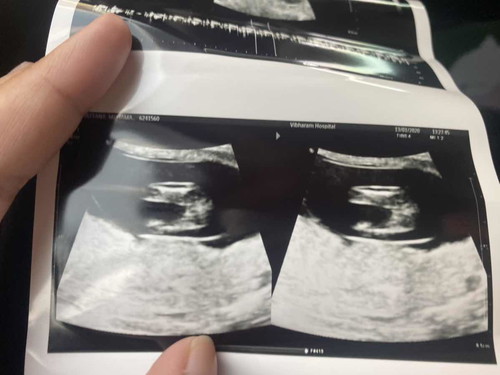

ตั้งครรภ์ได้15วีค ในใบซาวยังไม่มีอะไรแหลมๆโผล่ แบบนี้มีโอกาสที่จะได้ลูกสาวไหมค่ะแม่

บ้านนี้หมอคาดการณ์ว่าน่าจะได้ลูกสาวค่ะ เรียบไม่เห็นอะไรเลยค่าา😊